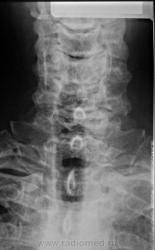

Соглашусь с коллегой Nela! Дегенеративные изменения шейного отдела позвоночника. Обызвествления передней продольной связки с образованием костных мостиков между телами позвонков. Деформирующий спондилез. Можно добавить остеохондроз(снижена высота дисков, склероз замыкательных пластин, артроз унко-вертебральных сочленений). Для Бехтерева - слишком зрелый возраст.

Диагноз основывается на данных рентгенографии позвоночника. Выявляется патогномоничный признак — оссификация передней продольной связки, первоначально в грудном отделе. В норме эта связка тонкая, при рентгенографии не видна, проходит вдоль всего позвоночника, огибает межпозвоночные диски и прикрепляется к телам позвонков; в результате оссификации эта связка становится рентгенопозитивной. Патологический процесс в связке обычно начинается в области тел позвонков, постепенно распространяется на другие отделы связки, что приводит к резкому и неравномерному ее утолщению (рис.), иногда до 10—20 мм. На рентгеновских снимках в прямой проекции в выраженных случаях позвоночник окружен по бокам лентовидными образованиями костной плотности с неровными контурами, как бы стекающими вдоль позвоночного столба, выгибаясь на уровне межпозвоночных дисков и соприкасаясь с телами позвонков. Позвоночник на определенных уровнях становится как бы закованным вновь образованной костной тканью (анкилозирующий гиперостоз позвоночника). Диагноз Ф. б. считается достоверным, если определяется непрерывное окостенение передней продольной связки на протяжении не менее четырех последовательных сегментов позвоночника вдоль переднелатеральной его части при условии отсутствия в этой области признаков остеохондроза, а также рентгенологических признаков сакроилеита. При рентгенографии различных отделов периферического скелета выявляются окостенение мест прикрепления сухожилий и связок к костям в виде шпор, бахромы, а иногда оссификация капсул суставов.

Анкилозирующийспондилоартрит(болезньБехтерева) можно включать в диф. ряд, только если видим анкилозирование межпозвонковых (межпозвоночных) суставов. В этом примере его нет!